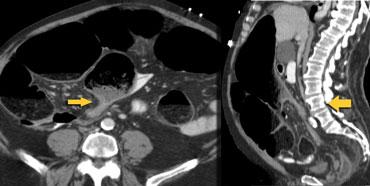

Ca lâm sàng bên trái cho thấy một bệnh nhân khác bị tắc ruột dạng quai kín.

Mặc dù các mạch máu ngấm thuốc tốt, nhưng dường như thành ruột không ngấm thuốc.

Các dấu hiệu thiếu máu cục bộ khác trong ca này bao gồm phù nề mạc treo và dày thành ruột.

Ruột bị nhồi máu được phát hiện trong quá trình phẫu thuật.

Nếu quai kín dài hơn và định hướng vuông góc với mặt phẳng cắt, chúng ta sẽ thấy một cụm quai ruột như trong ca lâm sàng bên trái.

Đôi khi điều này khó nhận biết chỉ trên các lát cắt ngang và các tái tạo mặt phẳng coronal hoặc sagittal có thể hữu ích.

Trong ca này, cũng có phù nề mạc treo và cổ